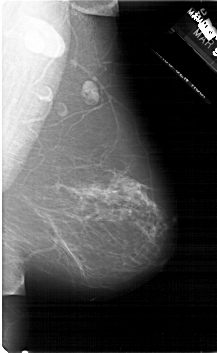

A_1300_1.LEFT_MLO

LEFT_MLO LINES 6166 PIXELS_PER_LINE 3946 BITS_PER_PIXEL 12 RESOLUTION 43.5 OVERLAY